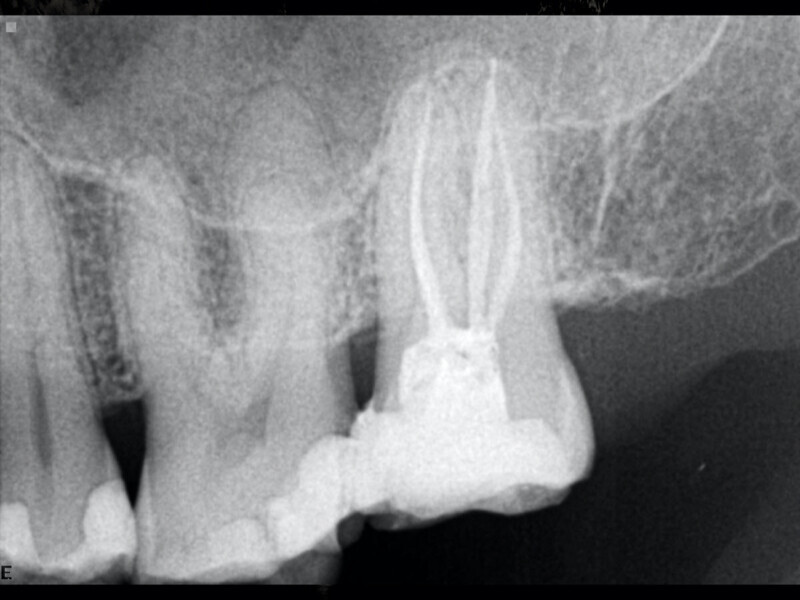

Clinical management of maxillary second molar root canal therapy in different anatomical situations